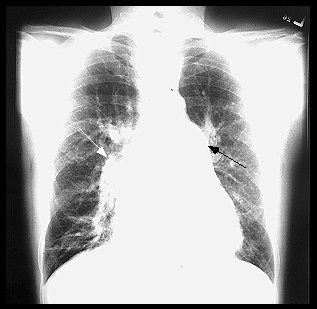

Rx cord-pulmon: circulatie pulmonara 'incarcata' cu ramurile AP dilatate in hiluri si extremitati 'retezate' avind periferie mult mai clara decat normal, bombare a conului arterei pulmonare, semne de hipertrofie VD

Imagine radiologica de HTP primara

Imagine radiologica de HTPS (DVPA) Imagine radiologica de HTPS (stenoza mitrala)

HTP secundara incipienta (DSA) HTPS severa (DSA Eisenmengerizat)

Imagine Rx. de profil cu HVD Aspect CT de HTP primara